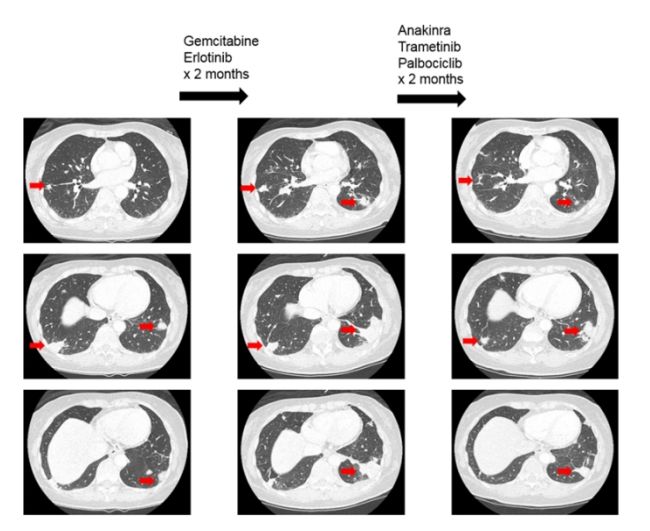

图4患者接受MEK抑制剂及其他靶向治疗案例

因此靶向RAS突变的药物,如MEK抑制剂可能会因大量共突变导致耐药,研究中观察到,RAS突变的多数患者携带的基因共突变可能起到了很重要的致癌作用(图1),因此如要有效的靶向抑制RAS可能需要同时抑制MEK通路及每个患者特异性的共出现的致癌突变。本研究证实,同时应用MEK抑制剂联合靶向匹配的共突变靶向药物可获得33%的客观缓解率,本研究中一例胰腺癌携带KRAS和CDKN2A突变,给予曲美替尼和哌柏西利治疗,部分缓解疗效维持了9个月,该患曾既往接受过含哌柏西利的治疗失败,但当时该方案中未包括MEK抑制剂,提示临床阶段这种治疗方式值得进一步探索。